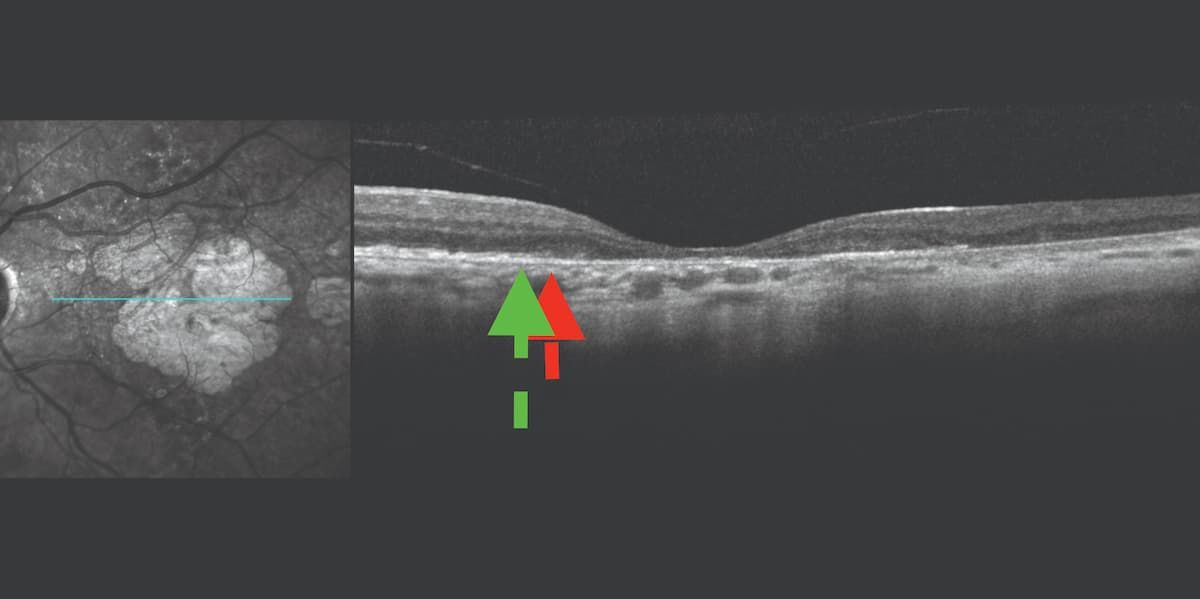

Multimodal imaging enables identification of the edge of RPE atrophy in relation to the retinal ellipsoid zone (EZ). FDA studies now accept the loss of that zone as an end point to show that a drug is preserving photoreceptors. Managing GA treatment has shown that patients with a significant loss of EZ are rapid progressors. If RPE atrophy and the EZ atrophy are the same on both sides of the lesion, that is likely to be a slow progressor, or it may not even be AMD. In that situation, I would monitor for change with follow-up in 3 to 6 months (Figure 4).

Figure 4: The Spectralis near-infrared and optical coherence tomography images demonstrate the edge of the ellipsoid zone (green arrow) compared with the edge of the retinal pigment epithelium (RPE) cell loss (red arrow). Note that the zone of photoreceptor cell loss is larger than the zone of RPE loss. This is characteristic of progressive geographic atrophy. (All figures courtesy of Jeremiah Brown Jr, MD, MS, FASRS)